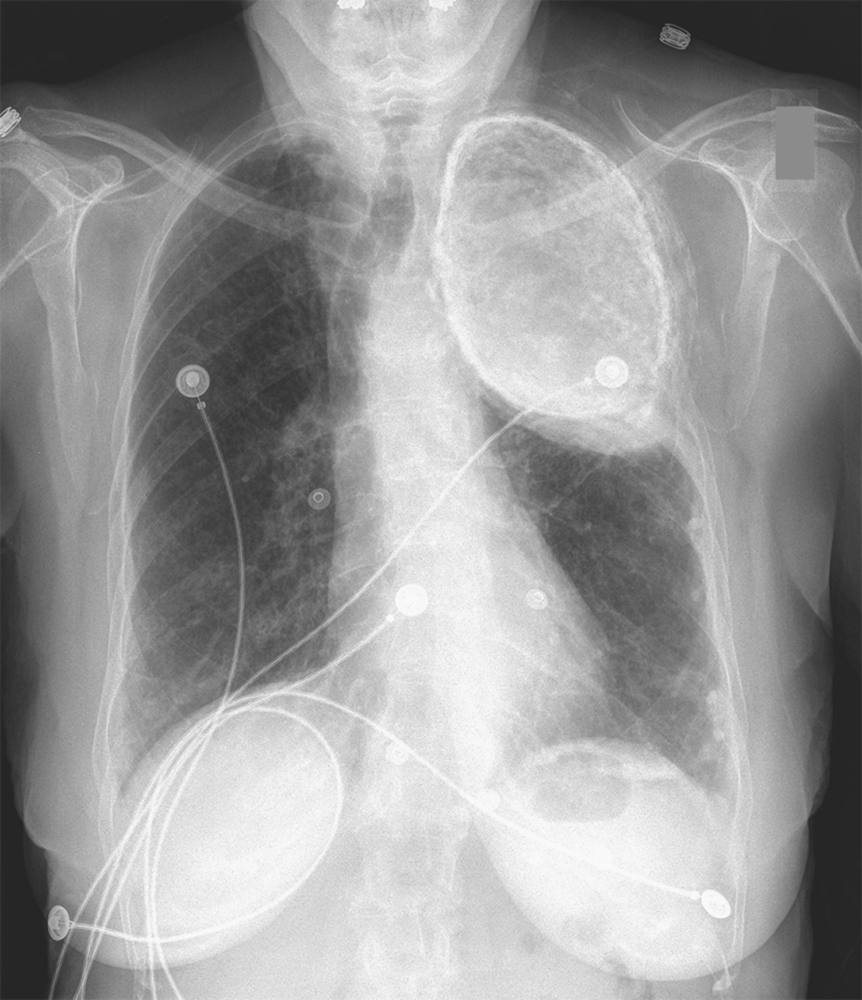

Incidental Finding on Chest X-Ray Post category:Spot Diagnosis Post published:May 5, 2023 Share on Facebook Share on X (Twitter) Share on Pinterest Share on Email Share on Reddit Incidental Finding on Chest X-Ray An 86-year-old woman with hypertension who had been treated for pulmonary tuberculosis in the 1950s presented with burning chest and epigastric pain. She had no respiratory symptoms. What is the diagnosis? FULL CASE AND ANSWER Share on Facebook Share on X (Twitter) Share on Pinterest Share on Email Share on Reddit Read more articles Previous PostSevere Pain and Blurred Vision in the Left Eye Next PostPainful Umbilical Nodule You Might Also Like Violaceous Plaque Consisting of Four Concentric Rings on Leg February 24, 2022 Pruritus and Papular Lesions Between Fingers, Axillae, Groin, and Buttocks September 22, 2021 Painless Erythematous Cutaneous Marks in a Fern-Leaf Pattern October 22, 2021